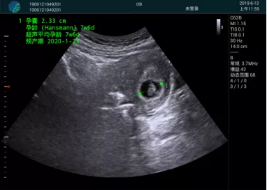

清晰顯示孕囊,通過軟件包計(jì)算孕齡7w+6d

M20實(shí)時(shí)引導(dǎo),術(shù)中清晰顯示孕囊被破壞和抽吸針的過程,清晰顯示吸引針

抽吸結(jié)束后縱切子宮,孕囊已被完全抽吸,未見明顯殘留

橫切子宮,發(fā)現(xiàn)右側(cè)宮腔靠近宮角處有少許脫模樣殘留

M20引導(dǎo)下,抽吸針找到右側(cè)宮角處再次清掃

二次抽吸后再次進(jìn)行超聲檢查,宮腔未見殘留,宮腔線清晰顯示